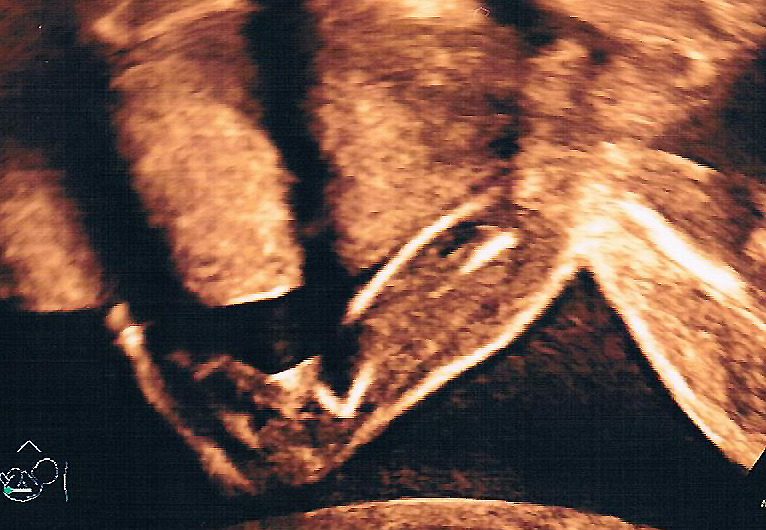

„Och, können Sie noch mal kurz beim Gesicht dran bleiben?“ bettele ich den Chefarzt der Frauenklinik in Coesfeld an und bin absolut begeistert von den Möglichkeiten des 3-D-Ultraschalls. Unter werdenden Mamas wird diese Art der Untersuchung auch häufig „Babyfernsehen“ genannt.

Der Chefarzt beginnt am Köpfchen und untersucht den Embryo Schritt für Schritt mit einer Menge Genauigkeit und Sorgfalt.

Fazit: 3-D-Ultraschall Bilder sind einfach klasse. In naher Zukunft gibt es „Babyfernsehen“ bestimmt komplett in Farbe.